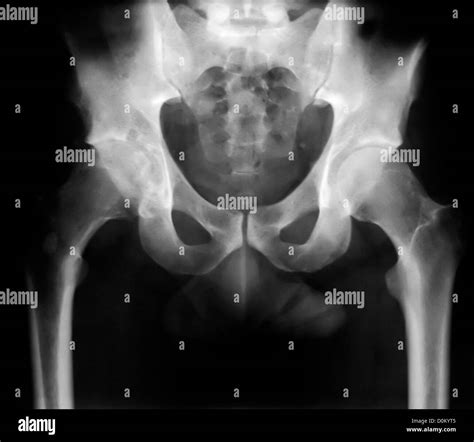

Normal Hip X Rays are a type of radiographic imaging used to visualize the hip joint and surrounding structures. This non-invasive procedure helps diagnose a wide range of conditions, including fractures, dislocations, arthritis, and developmental issues. The hip joint is a complex structure composed of the femoral head, acetabulum, and supporting ligaments and muscles. Normal Hip X Rays provide a clear view of these components, aiding in accurate diagnosis and treatment planning.

Interpreting Normal Hip X Rays requires a trained eye and a thorough understanding of hip anatomy. Radiologists look for specific features and measurements to determine the health of the hip joint. Key areas of focus include:

• Bone Density: Normal bone density indicates healthy bone structure. Any areas of decreased density may suggest osteoporosis or other bone diseases.

• Joint Space: The space between the femoral head and the acetabulum should be uniform and well-defined. Narrowing of this space can indicate arthritis or other degenerative conditions.

• Alignment: Proper alignment of the femoral head within the acetabulum is crucial. Misalignment can suggest dislocations, fractures, or developmental issues.

• Soft Tissue: While X-rays primarily focus on bone structures, they can also reveal abnormalities in soft tissues, such as swelling or calcification.